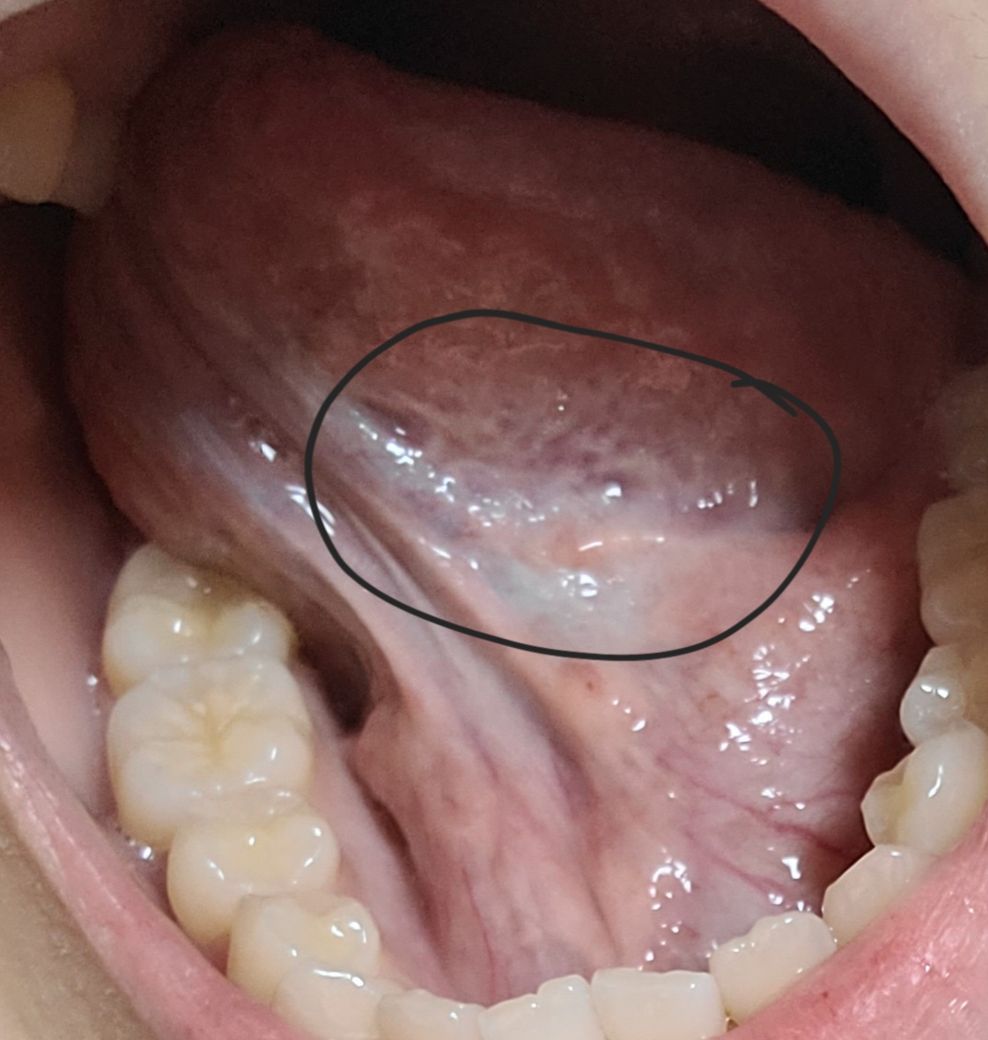

설암으로 보이는 백반증이 혀밑에 있어요 도와주세요ㅜㅜ

언제부터 있엇는진 모르겠는데 며칠전 확인해보니 혀 밑부분이 전체적으로 하얗게얼룩이 있고 3번째 사진처럼 혀밑 윗부분에도 얼룩이 있습니다 통증은전혀 없는데 저거 발견한 이후로 갑자기 혀가붓고 얼얼한느낌(아프진안음)도나요ㅜㅜ담배술은전혀안해요ㅜㅜ도와주세요 설암일확률 높나요

• 3번 째 사진

• 사진으로 봤을 경우에는 큰 문제가 있어 보이진 않습니다 너무 걱정하지 않으셔도 될 것으로 생각됩니다 걱정이 되신다면 치과에서 구강내과라는 과에서 진료를 받아보면 도움이 됩니다

• 설암의 양상으로 보이진 않습니다 걱정하시는 악성병소의 양상은 보통 출혈, 궤양, 불분명한 경계 등의 특징이 있습니다 구강내과에서 생검을 통해 보다 더 자세하게 확인해볼 수 있을 것 같습니다

• 현재 사진으로는 설암일 가능성은 거의 없으며, 통증 및 불편감이 있는 경우 우선 소독용 가글인 헥사메딘 가글액으로 가글하여 주길 권합니다. 통증 및 감각 이상 지속시에는 치과 진료를 받길 권합니다.